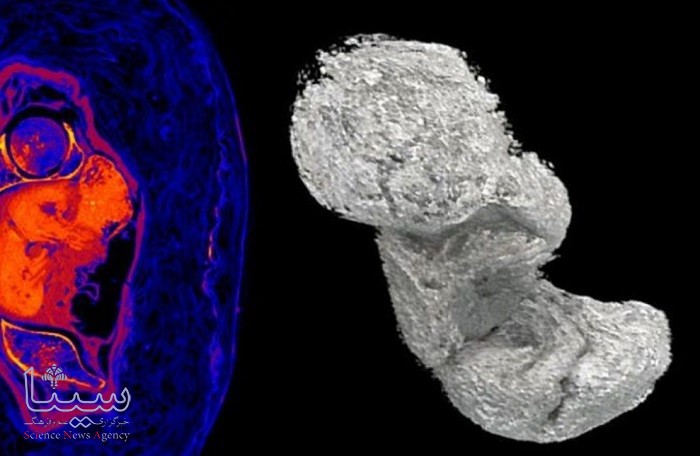

پژوهشگران در پی این کشف شگفت انگیز، تلاش کردند این نمونه منحصر به فرد را مورد مطالعه دقیق تری قرار دهند و به همین دلیل با استفاده از تصویربرداری توموگرافی مشخص شد که این زن در زمان مرگ بین ۲۰ تا ۳۰ سال سن داشته و در هفته ۲۶ تا ۳۰ بارداری خود بوده است.

در طول این فرآیند، جنین هنوز در رحم این زن قرار داشته و اساساً در یک محیط اسیدی واقع شده بود. به گفته پژوهشگران، اسید فرمیک و سایر ترکیبات (که پس از مرگ در رحم به دلیل فرآیندهای شیمیایی مختلف مربوط به تجزیه تشکیل می شوند) باعث تغییر Ph در بدن این زن می شود.

این فرایند پیچیده و تغییر از محیط قلیایی به اسیدی باعث حل شدن مواد معدنی از استخوان های جنین شده و سپس بافت بدن وی شروع به خشک شدن و معدنی شدن کرد. به گفته محققان، فرآیند مومیایی سازی مصری ها از دیدگاه شیمیایی، فرآیند کانی سازی بافت هایی است که می توانند هزاران سال زنده بمانند.

اوزارک زیلک در این رابطه گفت: این دو فرآیند به ما توضیح می دهند که چرا استخوان های جنین در سی تی اسکن به خوبی قابل مشاهده نیستند. برای مثال شما می توانید دست یا پاهای این جنین دو هزار ساله را ببینید، اما این اندام دارای استخوان نیستند، بلکه بافت های خشک شده ای هستند که شکل کلی دست یا پا را نشان می دهد. به گزارش سیناپرس، روند حل شدن استخوان های بدن این جنین در همه بخش های یکسان نبوده و جمجمه این جنین که سریع ترین رشد را داشته و معدنی ترین بخش بدن به شمار می رود تا حدی حفظ شده است.